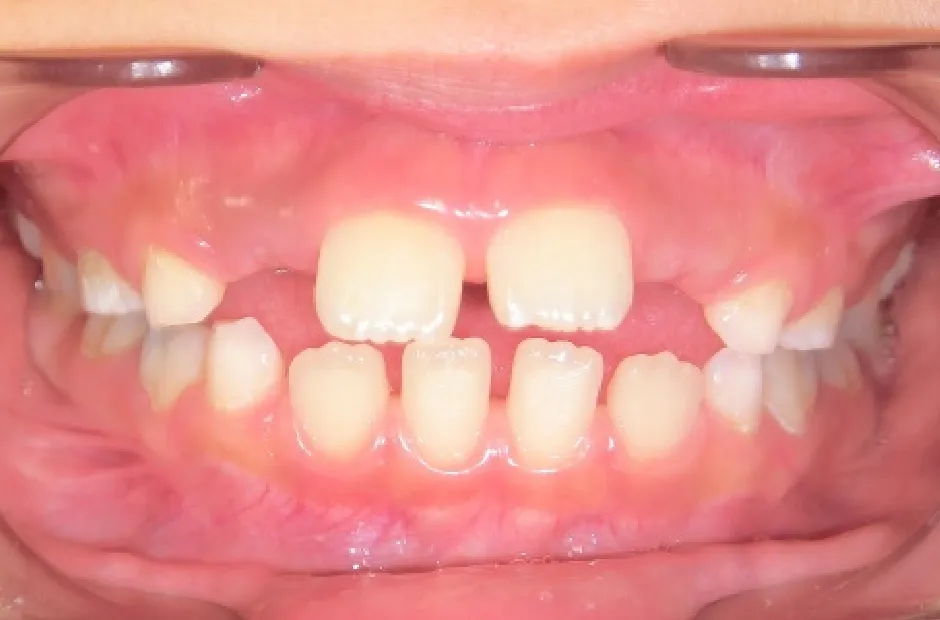

拡大床装置

叢生

| 診断名・主訴 | 叢生 |

|---|---|

| 年齢・性別 | 10歳・女性 |

| 治療期間・回数 | 2年半 |

| 治療に用いた主な装置 | 拡大床装置 |

| 抜歯部位 | なし |

| 治療費 | 30万円(税抜) |

| リスク・副作用 | 装置による違和感・疼痛・歯肉退縮・歯根吸収・虫歯のリスクなど |

治療前